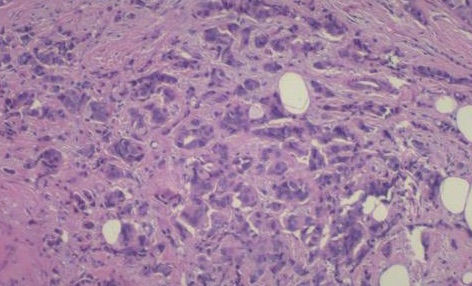

Pyoderma gangrenosum (PG) is a rare ulcerative disorder of the skin associated with underlying diseases, such as rheumatoid arthritis, inflammatory bowel disease and hematological malignancies. However, there have been very few reports of association of PG with solid organ malignancies. We report here the case of a 37-year-old lady with a chronic non-healing ulcer of the thigh, who repeatedly underwent multiple debridements, followed by two failed grafts, which was later diagnosed as PG. Initially, she failed to respond to oral steroids, but responded well with intravenous methylprednisolone pulse. However, she later presented with a breast mass with bone metastasis and recurrence of PG ulcer. Diagnosis and treatment of the underlying occult malignancy along with that of PG at an initial stage would have prevented the recurrence and avoided a serious consequence like metastasis. The case study underscores the association of PG with serious conditions, such as malignancy, and the necessity to conduct prompt and thorough analysis in such cases.